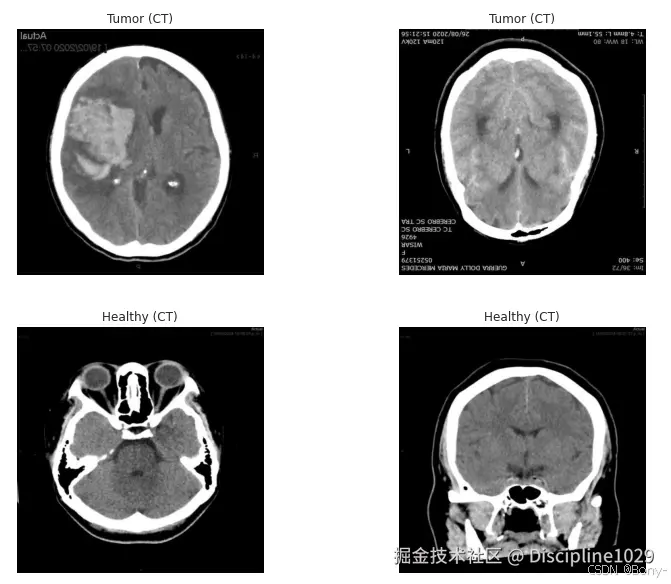

def show_random_images(df, label_filter, modality_filter, n=4):

subset = df[(df['label'] == label_filter) & (df['modality'] == modality_filter)]

n_to_show = min(n, len(subset))

sample_rows = subset.sample(n=n_to_show, random_state=42)

plt.figure(figsize=(12, 4))

for i, (_, row) in enumerate(sample_rows.iterrows(), start=1):

img_path = row['path']

img = cv2.imread(img_path)

plt.subplot(1, n_to_show, i)

plt.imshow(img)

lbl = "Tumor" if row['label'] == 1 else "Healthy"

mod = row['modality']

plt.title(f"{lbl} ({mod})")

plt.axis('off')

plt.tight_layout()

plt.show()

show_random_images(df, label_filter=1, modality_filter='CT', n=2)

show_random_images(df, label_filter=0, modality_filter='CT', n=2)

show_random_images(df, label_filter=1, modality_filter='MRI', n=2)

show_random_images(df, label_filter=0, modality_filter='MRI', n=2)

在这里插入图片描述 在这里插入图片描述